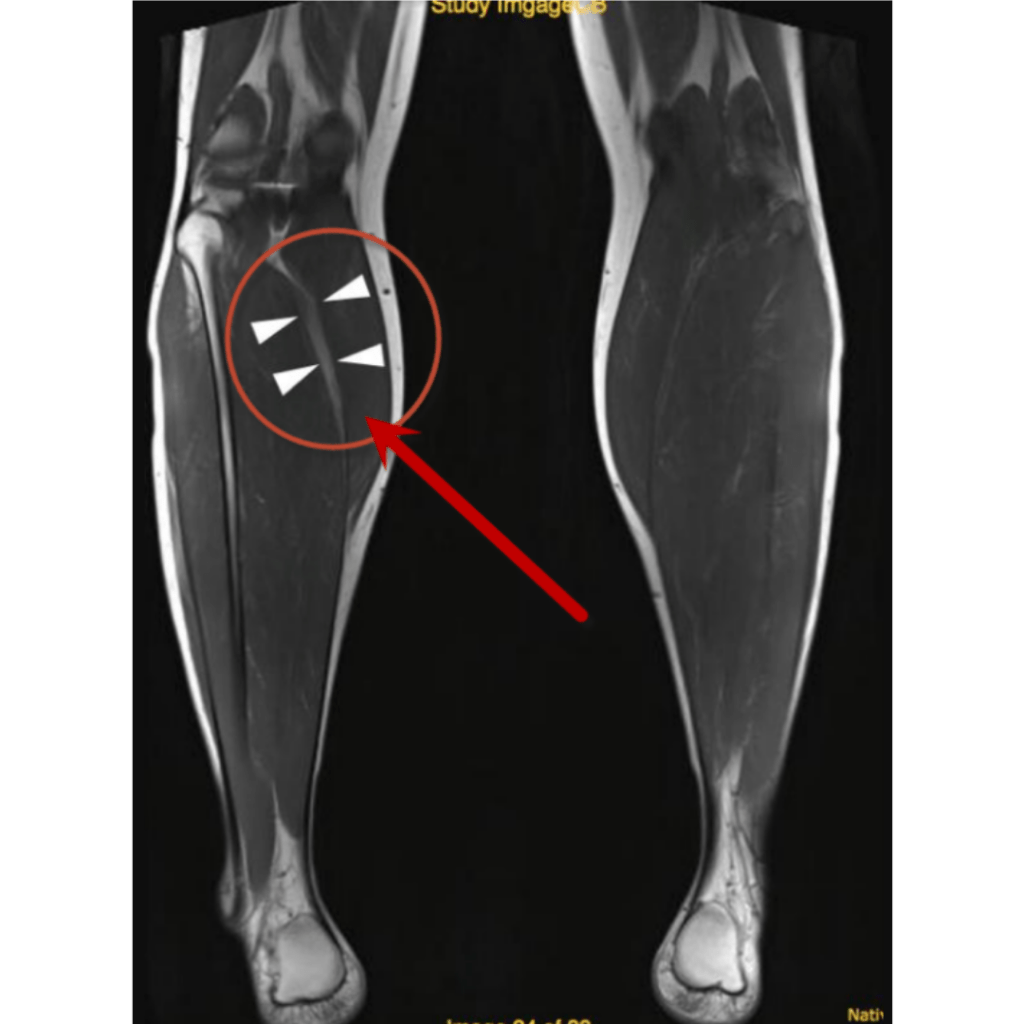

Resonancia magnética

Ruptura parcial Grado II